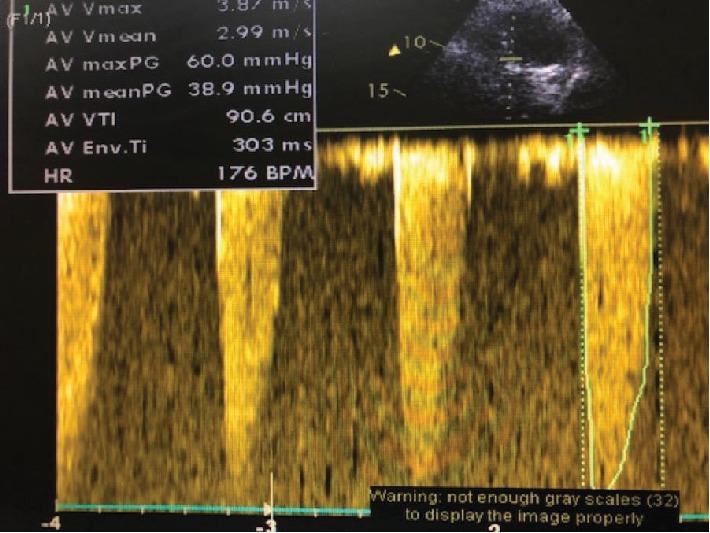

A single coronary artery is a rare congenital abnormality which consists of one coronary artery arising from the aortic trunk by a single coronary ostium and providing the perfusion of the entire myocardium. Its prevalence is approximately 0.024-0.066% of the population undergoing coronary angiography. A bicuspid aortic valve is the most common congenital cardiac abnormality and is found in 0.4-2.25% of the population. The coexistence of these two abnormalities together with severe aortic stenosis is extremely rarer. We report a patient who underwent transcatheter aortic valve implantation (TAVI) with a single coronary artery and a bicuspid valve. The procedure was successful, and the patient was discharged home without complication. To the best of our knowledge, this is the first report of these combined abnormalities and TAVI.

单冠状动脉是一种罕见的先天性异常,它由一条冠状动脉通过单一冠状动脉口从主动脉干发出,并为整个心肌提供灌注。其在接受冠状动脉造影的人群中的患病率约为0.024 - 0.066%。二叶式主动脉瓣是最常见的先天性心脏异常,在人群中的发生率为0.4 - 2.25%。这两种异常与严重主动脉瓣狭窄同时存在极为罕见。我们报告了一名患有单冠状动脉和二叶式瓣膜并接受经导管主动脉瓣植入术(TAVI)的患者。手术成功,患者出院时无并发症。据我们所知,这是关于这些合并异常和TAVI的首例报告。